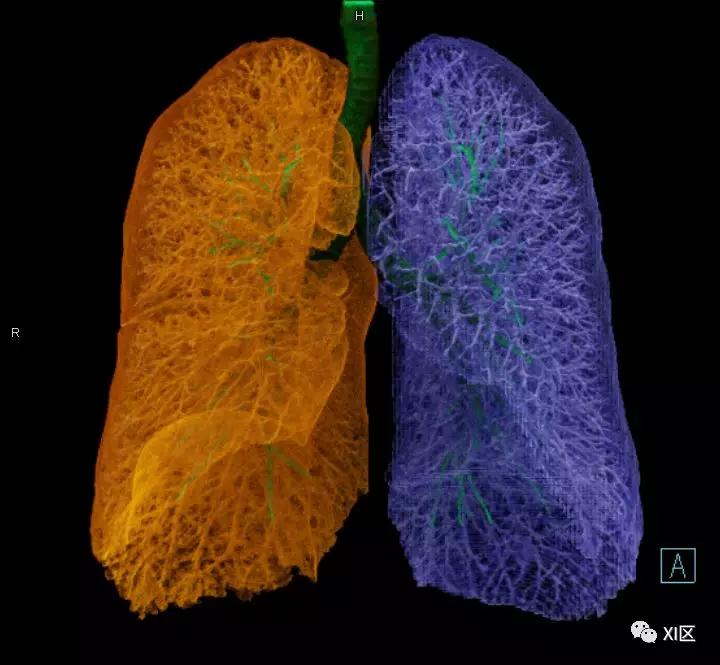

肺表面重建显示叶间裂和肺的分叶

透视图显示肺的叶间裂和肺的分叶

左肺借斜裂成上、下两叶;右肺借斜裂和水平裂成上、中和下叶三叶。